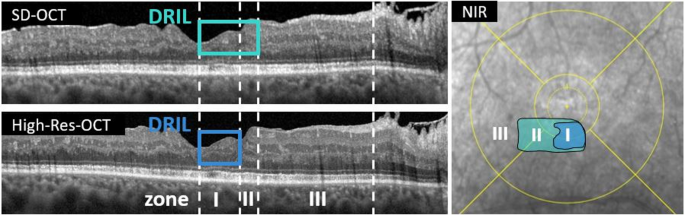

Based on our previous study, we defined three OCT-based zones: (I) DRIL detectable on both OCT devices (abbr. High-Res DRIL), (II) DRIL detectable in SD-OCT, but not High-Res OCT (abbr. SD-/High-Res DRIL), and (III) no visible pathologies on both OCT devices (abbr. no DRIL). (Fig. 1). For the intra-eye zone analysis, only stimuli located within DRIL or non-pathological areas were included to avoid confounding effects of coexisting biomarkers (ME or DROL). This grading was performed on a stimulus-by-stimulus rather than a patient level. It should be noted that these “zones” do not correspond to anatomical ETDRS subfields but represent modality-based classifications within DRIL eyes.

Macular B-scan of SD- and High-Res OCT and near-infrared reflectance (NIR) image of a 49-year-old patient with DRIL. DRIL is defined as the loss of discernibility of the inner retinal layers, including RNFL, GCL, IPL, INL, and OPL. Compared to SD-OCT, the High-Res OCT allows for clearer layer differentiation and reveals significantly smaller DRIL areas. This difference is visualized in the NIR image with en face overlays: DRIL areas detected on SD-OCT are marked in turquoise, while those detected on High-Res OCT are shown in blue. Based on these findings, three zones were defined: (I) DRIL detectable on both OCT modalities, (II) DRIL detectable on SD-OCT but not on High-Res OCT, and (III) no DRIL detectable on either modality.